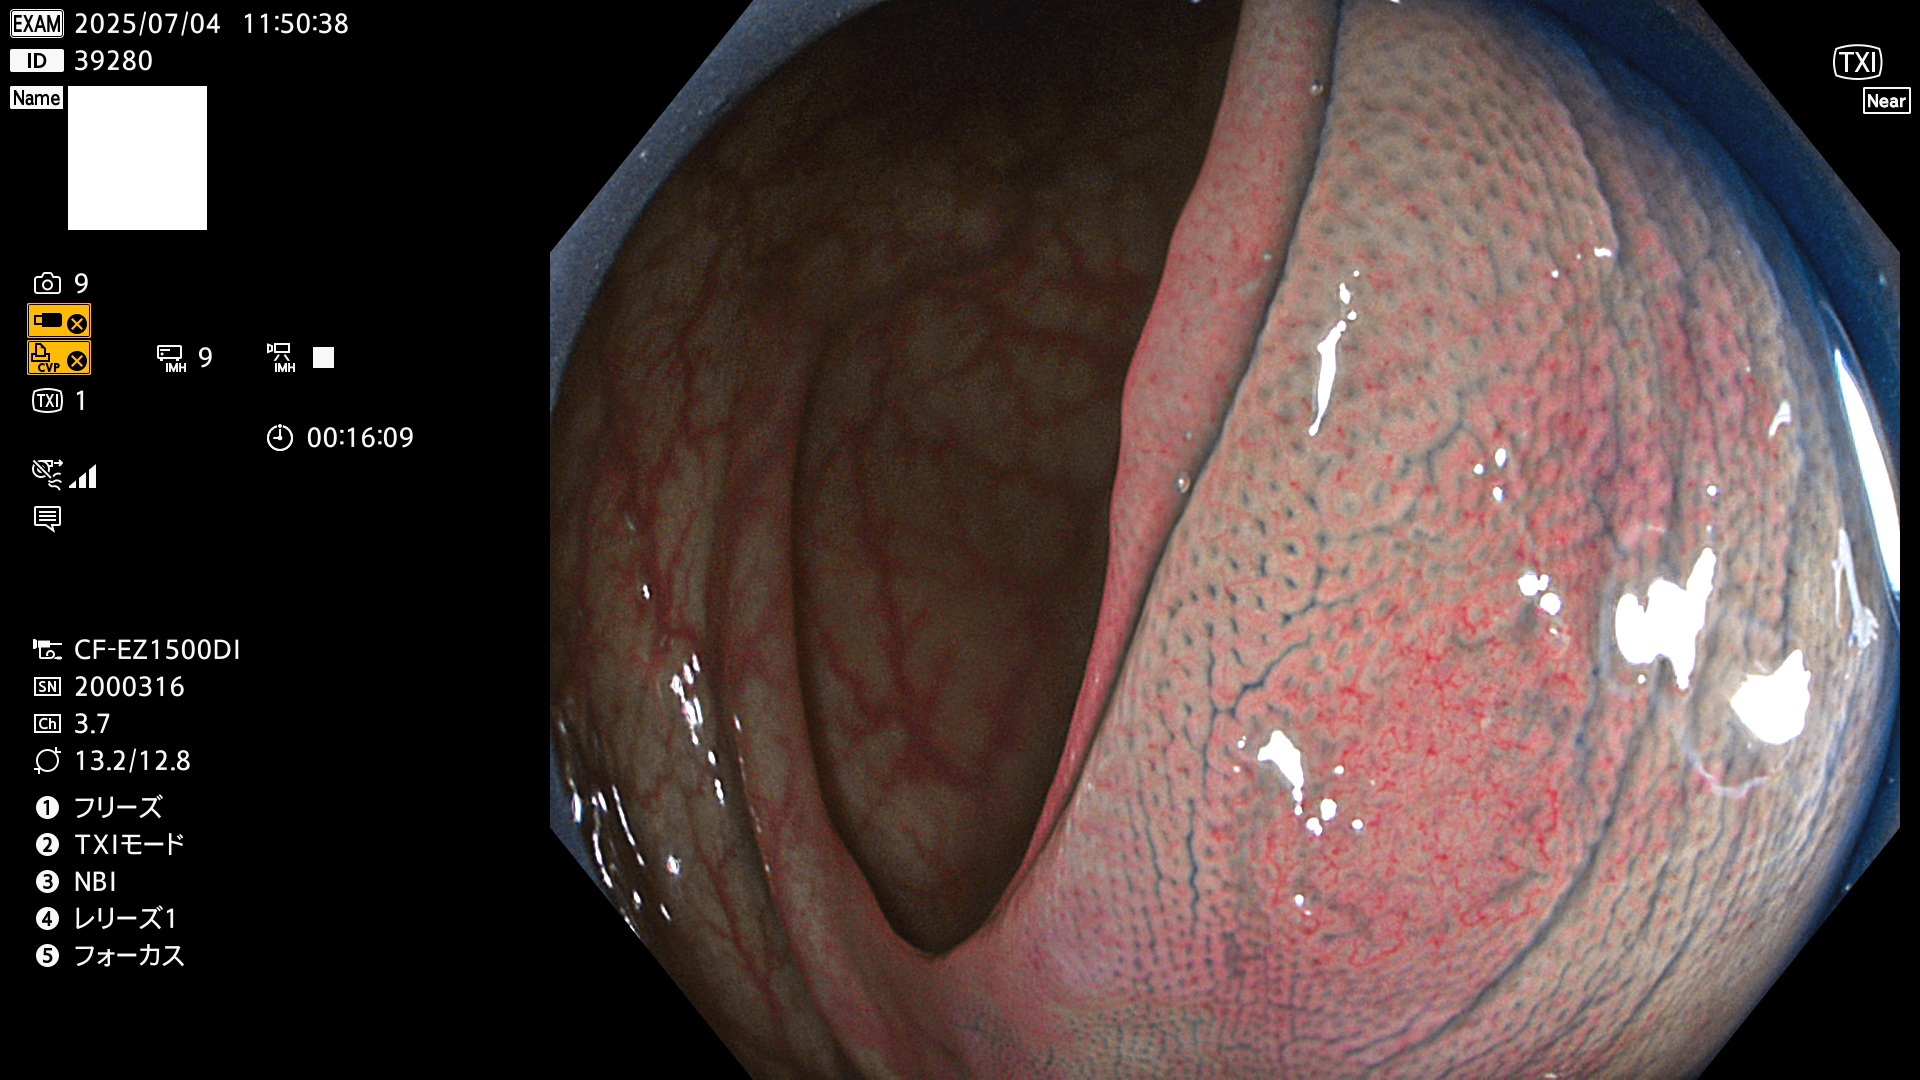

2025年7月3日〜7月6日の4日間(40件)8個 (Uc_ADR=8/40=20%)

完全に平坦な物をUb、陥凹している物をUcと呼びます。Ubは認識が困難で、Ucはびらん(炎症)と紛らわしいために見落とされやすく、「内視鏡後・大腸癌」の原因になります。